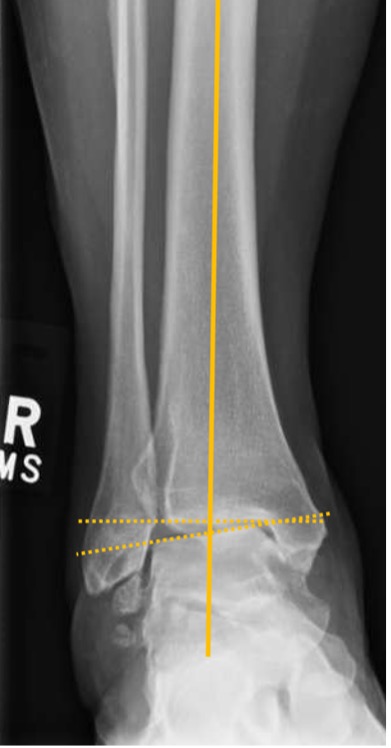

Figure 5. Measuring the deformity

- MDTA (TAS) is crucial for quantifying the supramalleolar deformity (Fig. 3)

- TTA normally defines the centre of rotation of angulation (CORA)

- Talar tilt should be used for quantitative assessment of an intra-articular deformity in the coronal plane. It is defined as the difference between the MDTA and the TTA

Talus tilt (TTA) = TTS – mDTAA

- Values of >4° are considered to be pathological